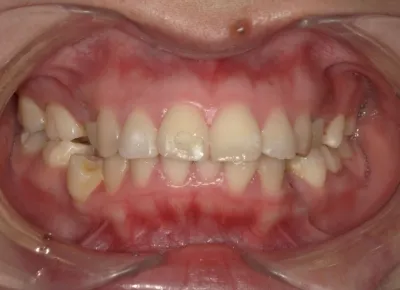

Before

After

治療期間

費用総額